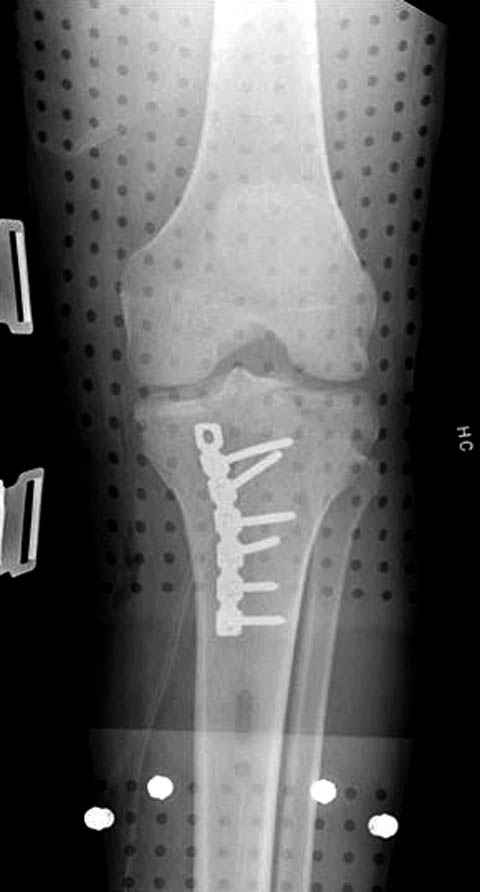

Трудно поверить, что разрекламированная Ортопедическая школа Восточной Украины позволяет такие странные снимки? На прямом снимке сохранен общий контур плато, но не известна судьба импрессии суставной поверхности. На полубоковой?, оставлен без репозиции задне-медиальный отдел, и навряд ли после такой фиксации можно удовлетвориться результатом.

Такая ситуация характерна для многих, когда принимается ошибочное решение, т.е пытаются фиксировать одним имплантом переломы двух мыщелков. Латеральная пластина приемлема только для тех случаев, когда сохраняется интактным медиальный диафизарный кортекс и отсутствует фрагментация на верхушке медиального перелома.